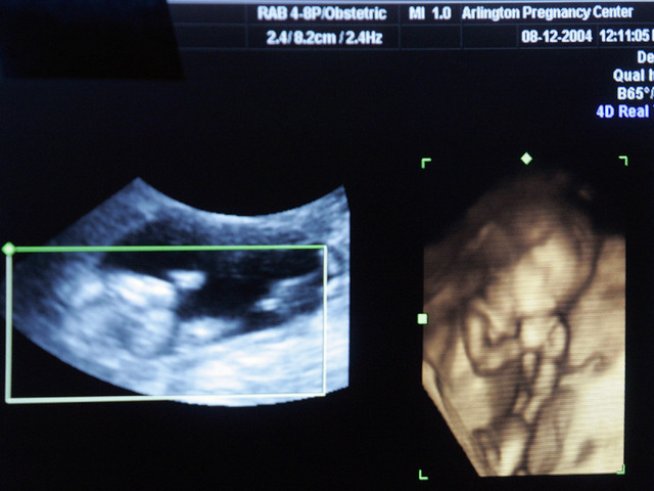

Снимка: Reuters